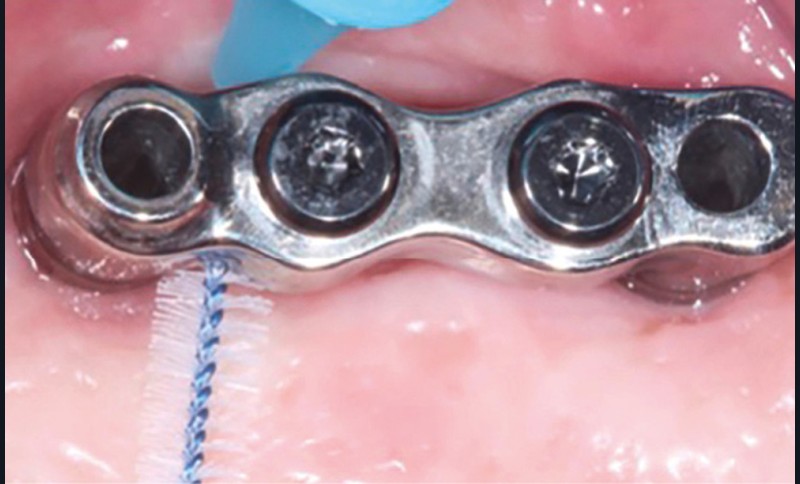

Enfin, la conception prothétique elle-même est à réfléchir, que ce soit en termes de profil d’émergence [18, 19] (pas de surcontour par exemple) (fig. 8) que d’accès à l’hygiène [20, 21] (fig. 9).